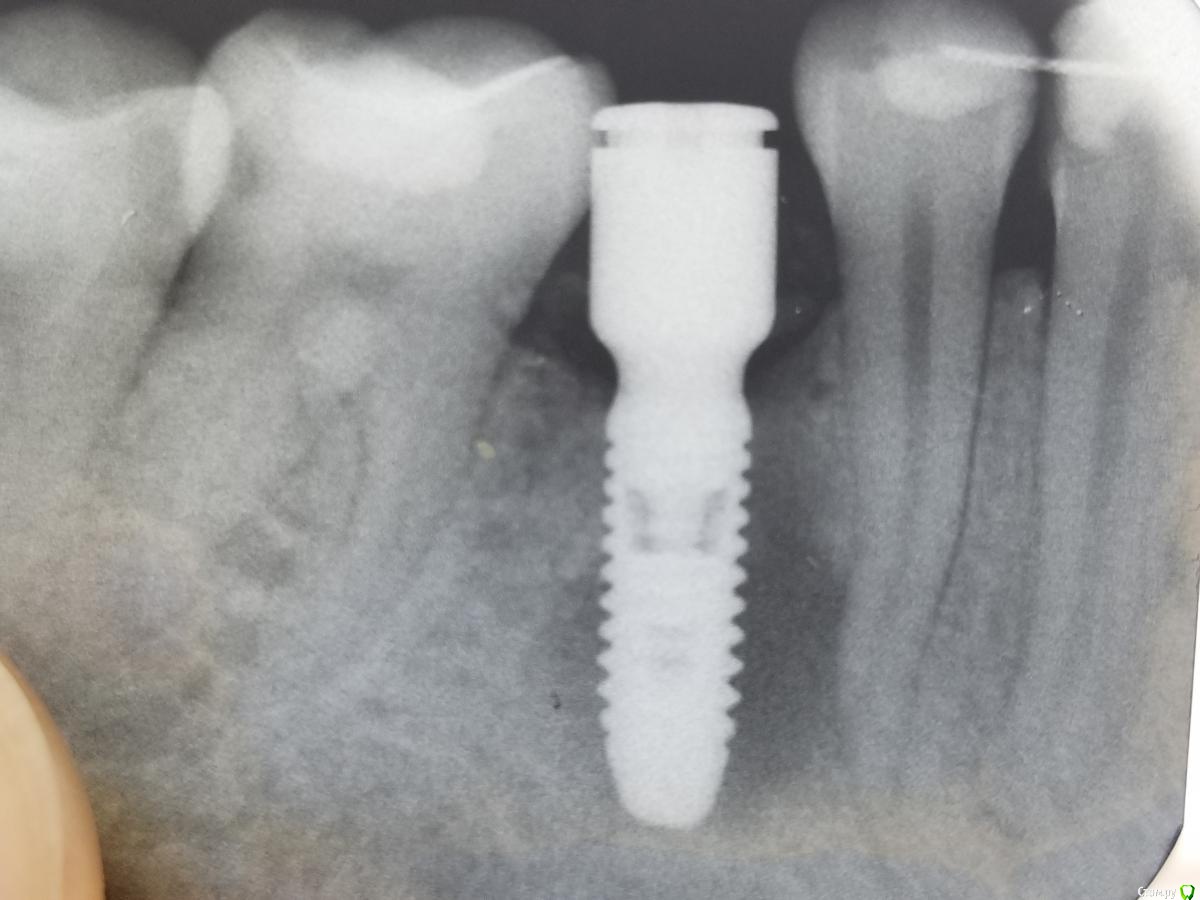

___49___ Опубликовано 10 февраля, 2019 Поделиться Опубликовано 10 февраля, 2019 Спасибо, что делитесь подобными работами ( а не только когда все в ажуре) . Резекцию верхушки импланта вижу впервые ..... очень интересно дальнейшее развитие событий . Скажите пожалуйста с чем связываете данную проблему ? не боитесь рецессии в виду такого доступа к резекции , все-таки питающие стволики сосудов пересечены ... 1 Ссылка на комментарий

AlexanderGudkov Опубликовано 10 февраля, 2019 Автор Поделиться Опубликовано 10 февраля, 2019 Спасибо, что делитесь подобными работами ( а не только когда все в ажуре) . Резекцию верхушки импланта вижу впервые ..... очень интересно дальнейшее развитие событий . Скажите пожалуйста с чем связываете данную проблему ? не боитесь рецессии в виду такого доступа к резекции , все-таки питающие стволики сосудов пересечены ...Не знаю, в чем причина. Наука говорит, что единственная причина - инфекция. Хотя при санации очага содержимое не походило на грануляции. Еще определялось сообщения очага с резцовым каналом, может дремлющая киста канала напала на имплант..))) Ссылка на комментарий

Lodkin666 Опубликовано 11 февраля, 2019 Поделиться Опубликовано 11 февраля, 2019 Александр, каким бором пилили? Тяжело ли пилится имплант? В таких случая костный материал используется? Ссылка на комментарий

AlexanderGudkov Опубликовано 11 февраля, 2019 Автор Поделиться Опубликовано 11 февраля, 2019 Александр, каким бором пилили? Тяжело ли пилится имплант? В таких случая костный материал используется?Длинный золотистый ссвайт по металлу, пилится очень легкоГрафт не сыпал, не хотел чтобы на снимках он мешал наблюдать за заживлением Ссылка на комментарий